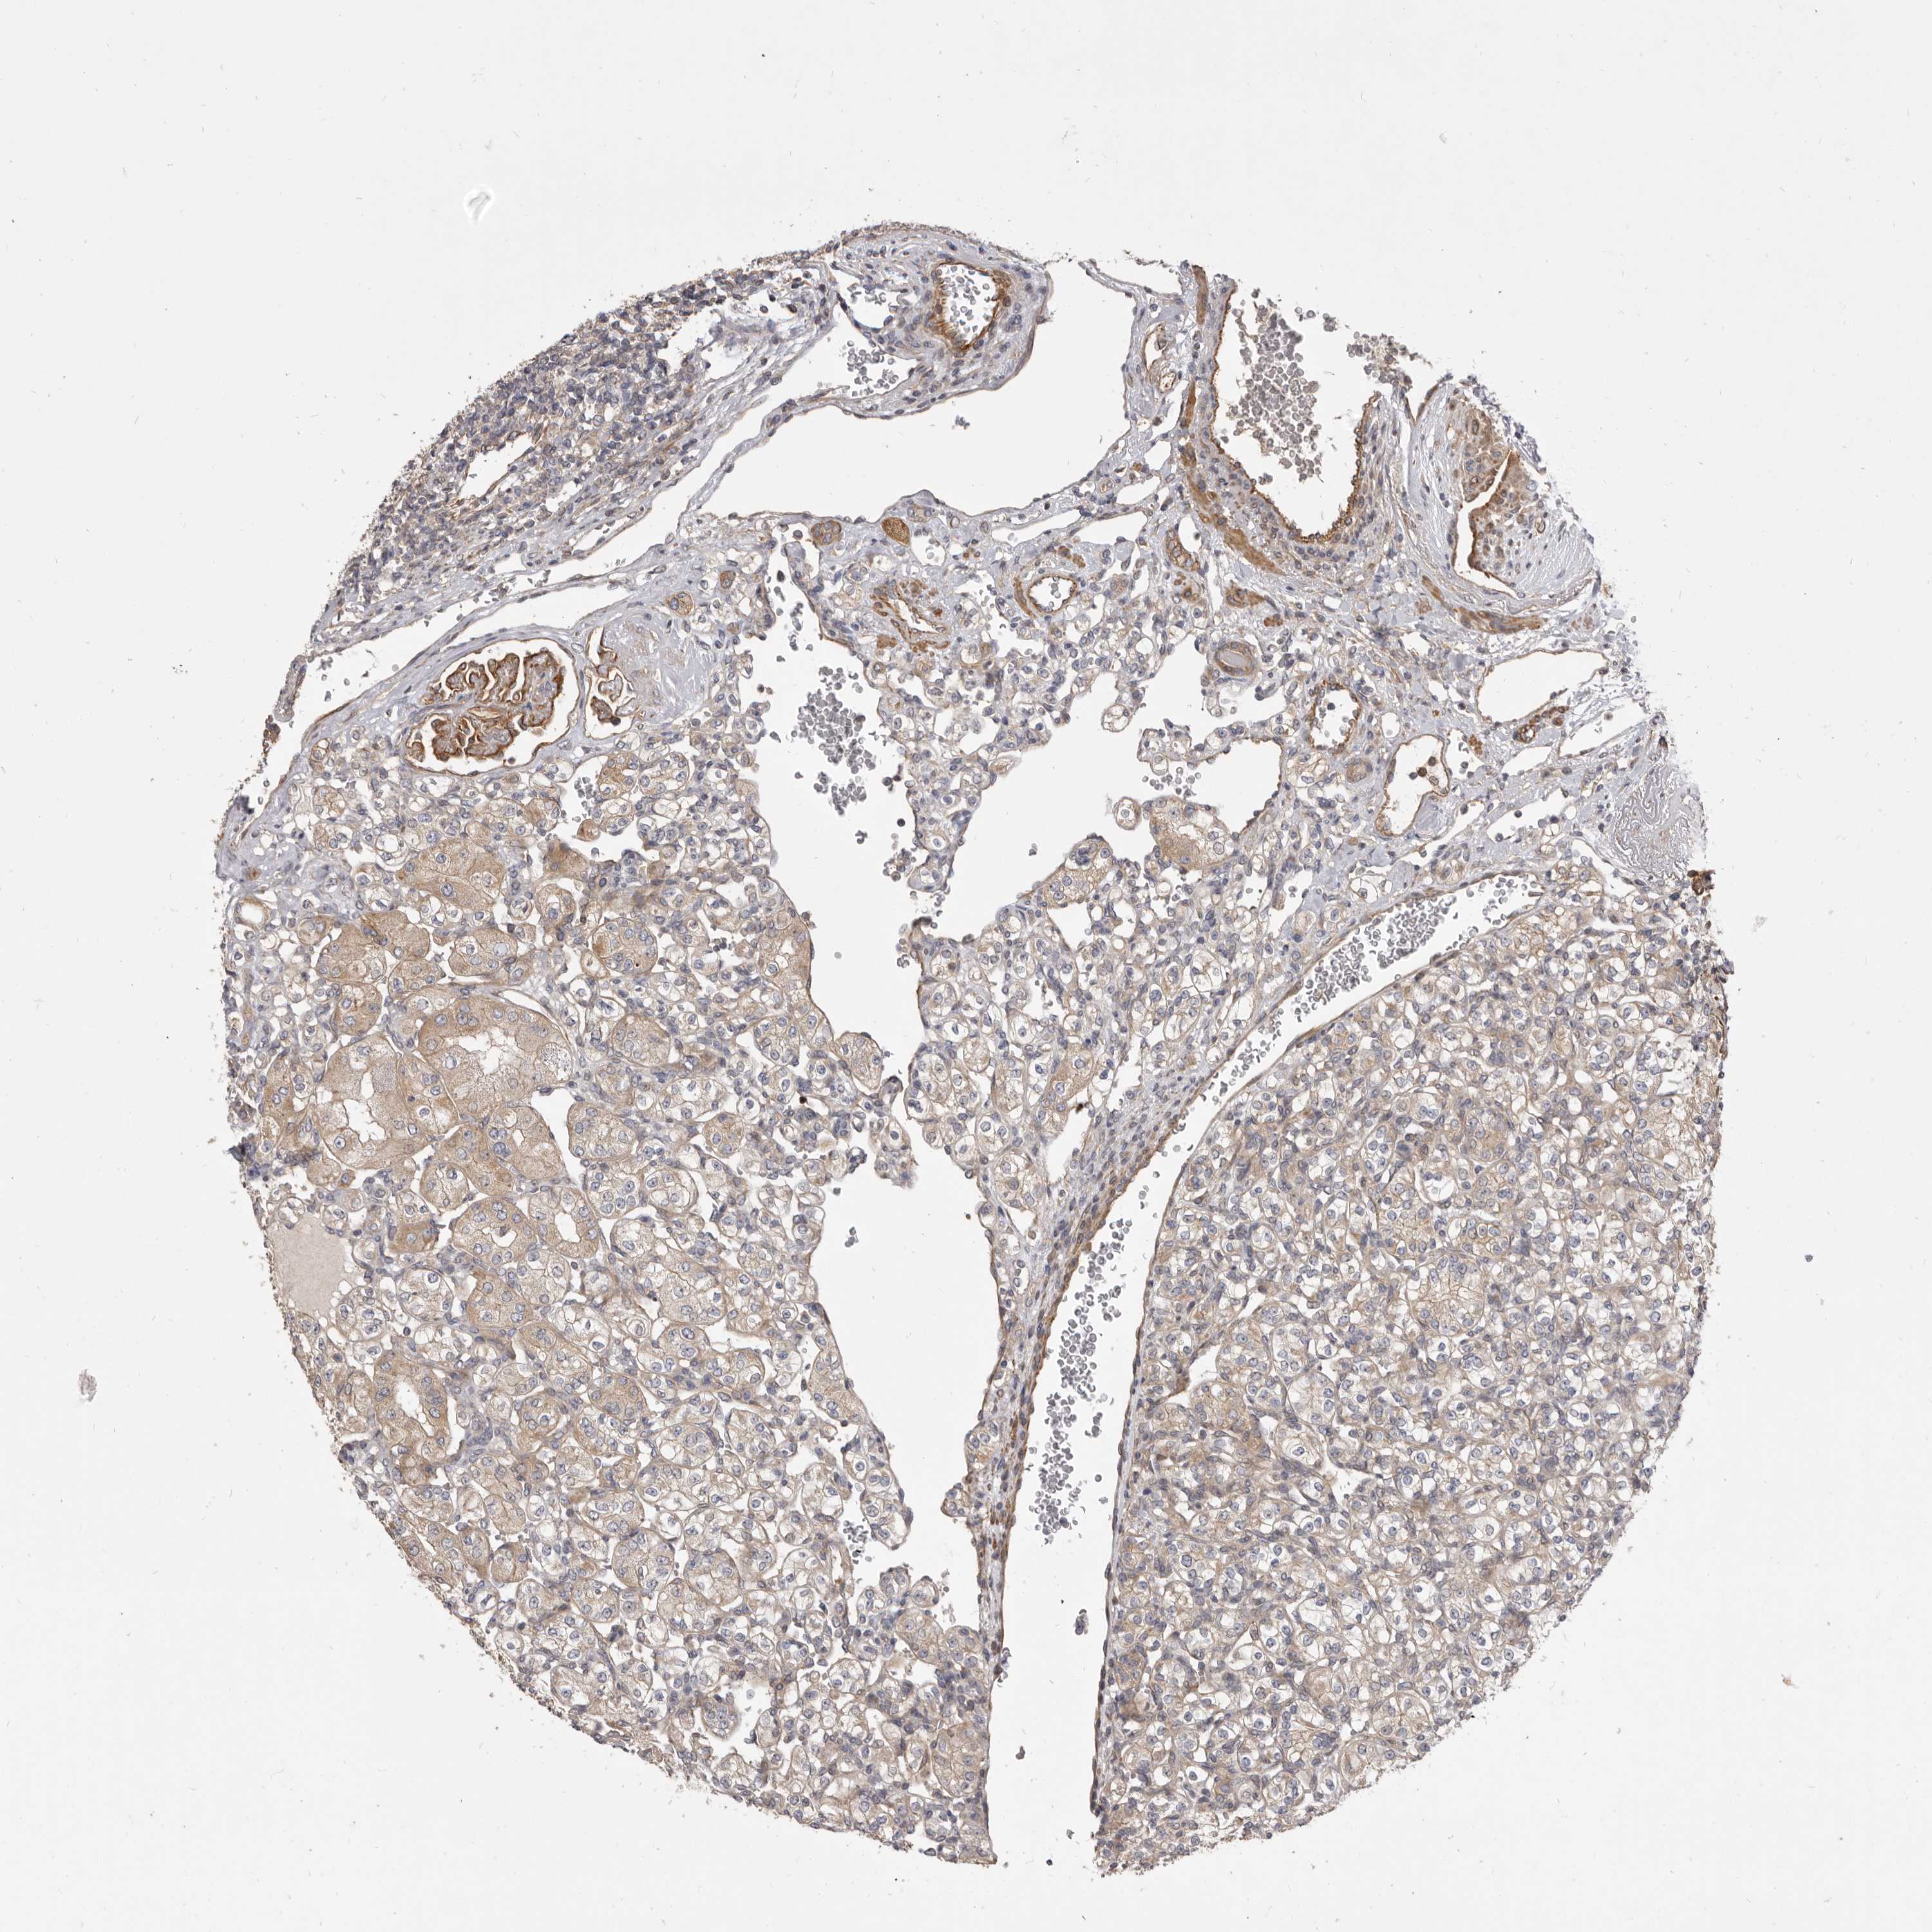

KIDNEY RENAL CLEAR CELL CARCINOMA (VALIDATION) - Interactive survival scatter ploti

The Survival Scatter plot shows the clinical status (i.e. dead or alive) for all individuals in the patient cohort, based on the same data that underlies the corresponding Kaplan-Meier plots. Patients that are alive at last time for follow-up are shown in blue and patients who have died during the study are shown in red.

The x-axis shows the expression levels (FPKM) of the investigated gene in the tumor tissue at the time of diagnosis. The y-axis shows the follow-up time after diagnosis (years). Both axes are complimented with kernel density curves demonstrating the data density over the axes. The top density plot shows the expression levels (FPKM) distribution among dead (red) and alive patients (blue). The right density plot shows the data density of the survived years of dead patients with high and low expression levels respectively, stratified using the cutoff indicated by the vertical dashed line through the Survival Scatter plot. This cutoff is automatically defined based on the FPKM cutoff that minimizes the p-score. The cutoff can be changed by dragging the vertical line or by entering a cutoff value in the square labeled "Current cut-off".

Under the Survival Scatter plot the p-score landscape (black curve; left axis) is shown together with dead median separation (red curve; right axis). Dead median separation is the difference in median mRNA expression between patients who have died with high and low expression, respectively. It is calculated as follows: median FPKM expression of dead patients with high expression - median FPKM expression of dead patients with low expression. This is intended to aid the user in visually exploring custom cutoffs and the associated p-scores and dead median separation.

Individual patient data is displayed and can be filtered by clicking on one or more of the category buttons on the top of the page. Categories describing expression level and patient information include: high, low, alive, dead, female, male and tumor stages. The scale of the x-axis can be toggled between linear and log-scale by clicking on the "x log" button. Mouse-over function shows TCGA ID, patient information and mRNA expression (FPKM) for each patient.

& Survival analysisi

Kaplan-Meier plots summarize results from analysis of correlation between mRNA expression level and patient survival. Patients were divided based on level of expression into one of the two groups "low" (under cut off) or "high" (over cut off). X-axis shows time for survival (years) and y-axis shows the probability of survival, where 1.0 corresponds to 100 percent.

VPS45 is not prognostic in Kidney Renal Clear Cell Carcinoma (validation)

: 20.28

Average pTPM 19.3

Number of samples 100